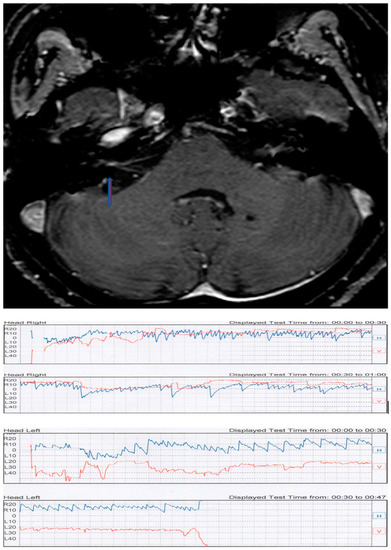

| BM | female | 81 | intrameatal (0.3 cm) | left | left PSC PPN | first sign | not responsive |